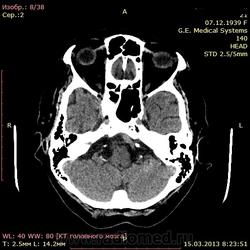

А как по мне, то тут геморрагический инсульт. Есть дислокация срединных структур слева.

Геморрагический инфаркт левой височной доли (в проекции таламуса слева) как правильно по локализации сам не знаю, скорее все таки таламус, со смещением срединных структур вправо, третий и левый боковой желудочек частично компримированы, формируется зона перифокального отека

тут либо геморрагический инсульт с перифокальным отеком, либо ишемический инсульт с геморагическим пропитыванием. Как их различить? Что скажут опытные коллеги?

Типичное медиальное кровоизлияние (в таламусе, медиальнее внутренней капсулы), уже не совсем свежее, плотность уже более низкая и зона отека приличная.

КТ признаки кровоизлияния в базальных ядрах, отделах с выраженными признаками перифирического отека. Про давность - сами пусть спросят , но скорее не свежак, до 5-6 дней.

Описывайте как геморрагический инсульт с объемным действием (смещением) на срединные структуры мозга. Померяйте плотности для оценки стадии. А различить на КТ две обговариваемые формы думаю нельзя. Разве что при пропитывании не будет такой четкой динамики изменения плотности очага. В литературе не встречал.